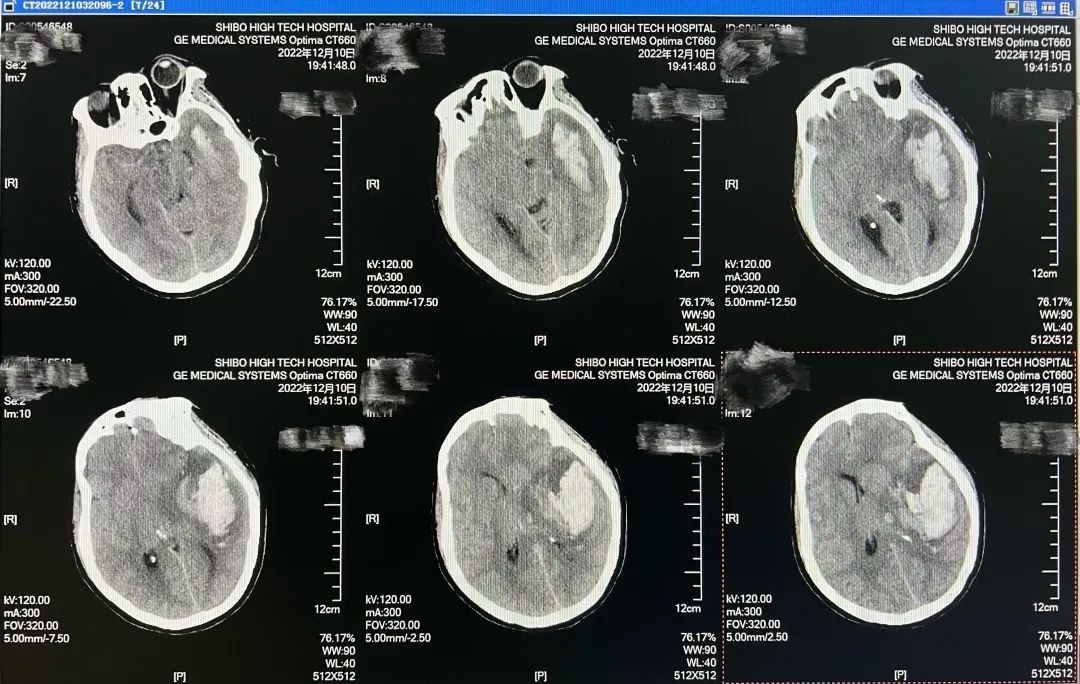

12月10日晚间,胡大娘(化名)在家中突发头痛、头晕,出现恶心、呕吐、意识不清、呼之不应,伴有肢体抽搐、小便失禁,被家属急送入世博高新医院急诊科。就地进行核酸采样后,患者被送入急诊CT室进行颅脑CT检查,结合影像结果确诊为左侧丘脑及左侧额颞顶部脑出血,破入脑室并形成脑疝。病情凶险,生命垂危,必须立即手术。